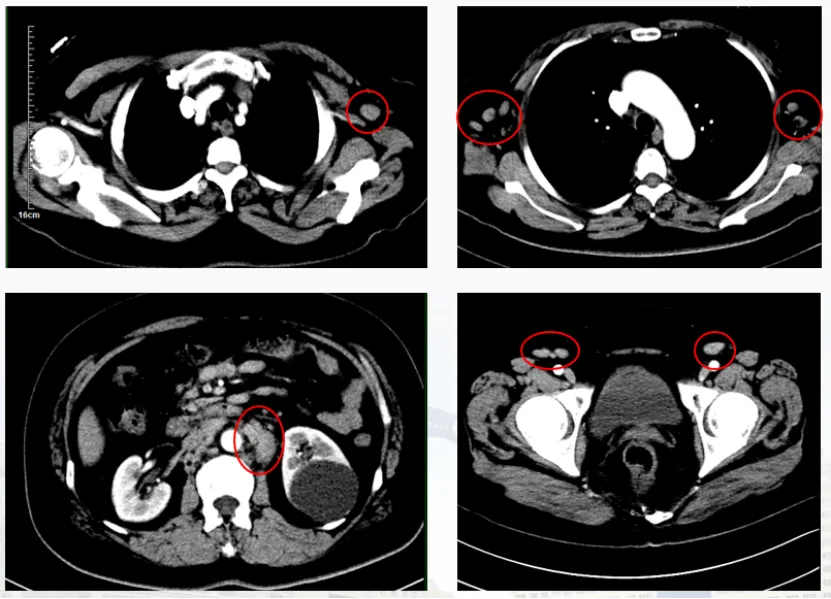

基因检测揪出 “隐藏凶手”:一例CCDC88C::PDGFRB融合基因阳性MLN-TK靶向治疗奇迹

病史摘要:15 岁男性患者,2018 年 9 月因双侧颈部淋巴结进行性肿大就诊。无其他特殊既往史。现以双侧颈部淋巴结肿大为主要表现,左侧 10cm×7cm,右侧 10cm×5cm。 诊疗过程:实验室检查示白细胞增高伴显著嗜酸性粒细胞增多、轻度贫血。左颈部淋巴结穿刺活检考虑为 T 淋巴母细胞淋巴瘤/白血病。PET/CT 显示多区域淋巴结受累等。骨髓 MICM 分型检查有相应表现。初诊为 T